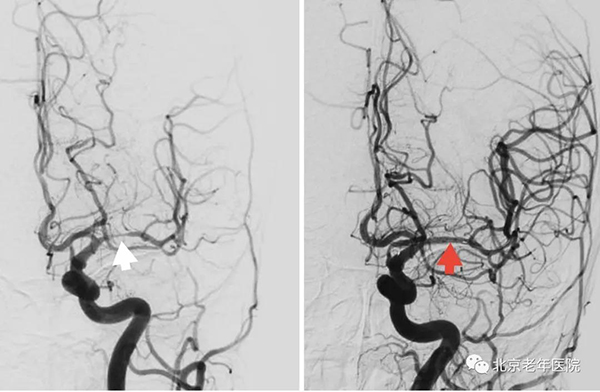

术中造影显示:左侧大脑中动脉M1段重度狭窄(白箭头)。全麻下同期行左侧大脑中动脉球囊扩张术及支架置入术(红箭头)。手术过程顺利,无不良事件发生,患者术后恢复良好。